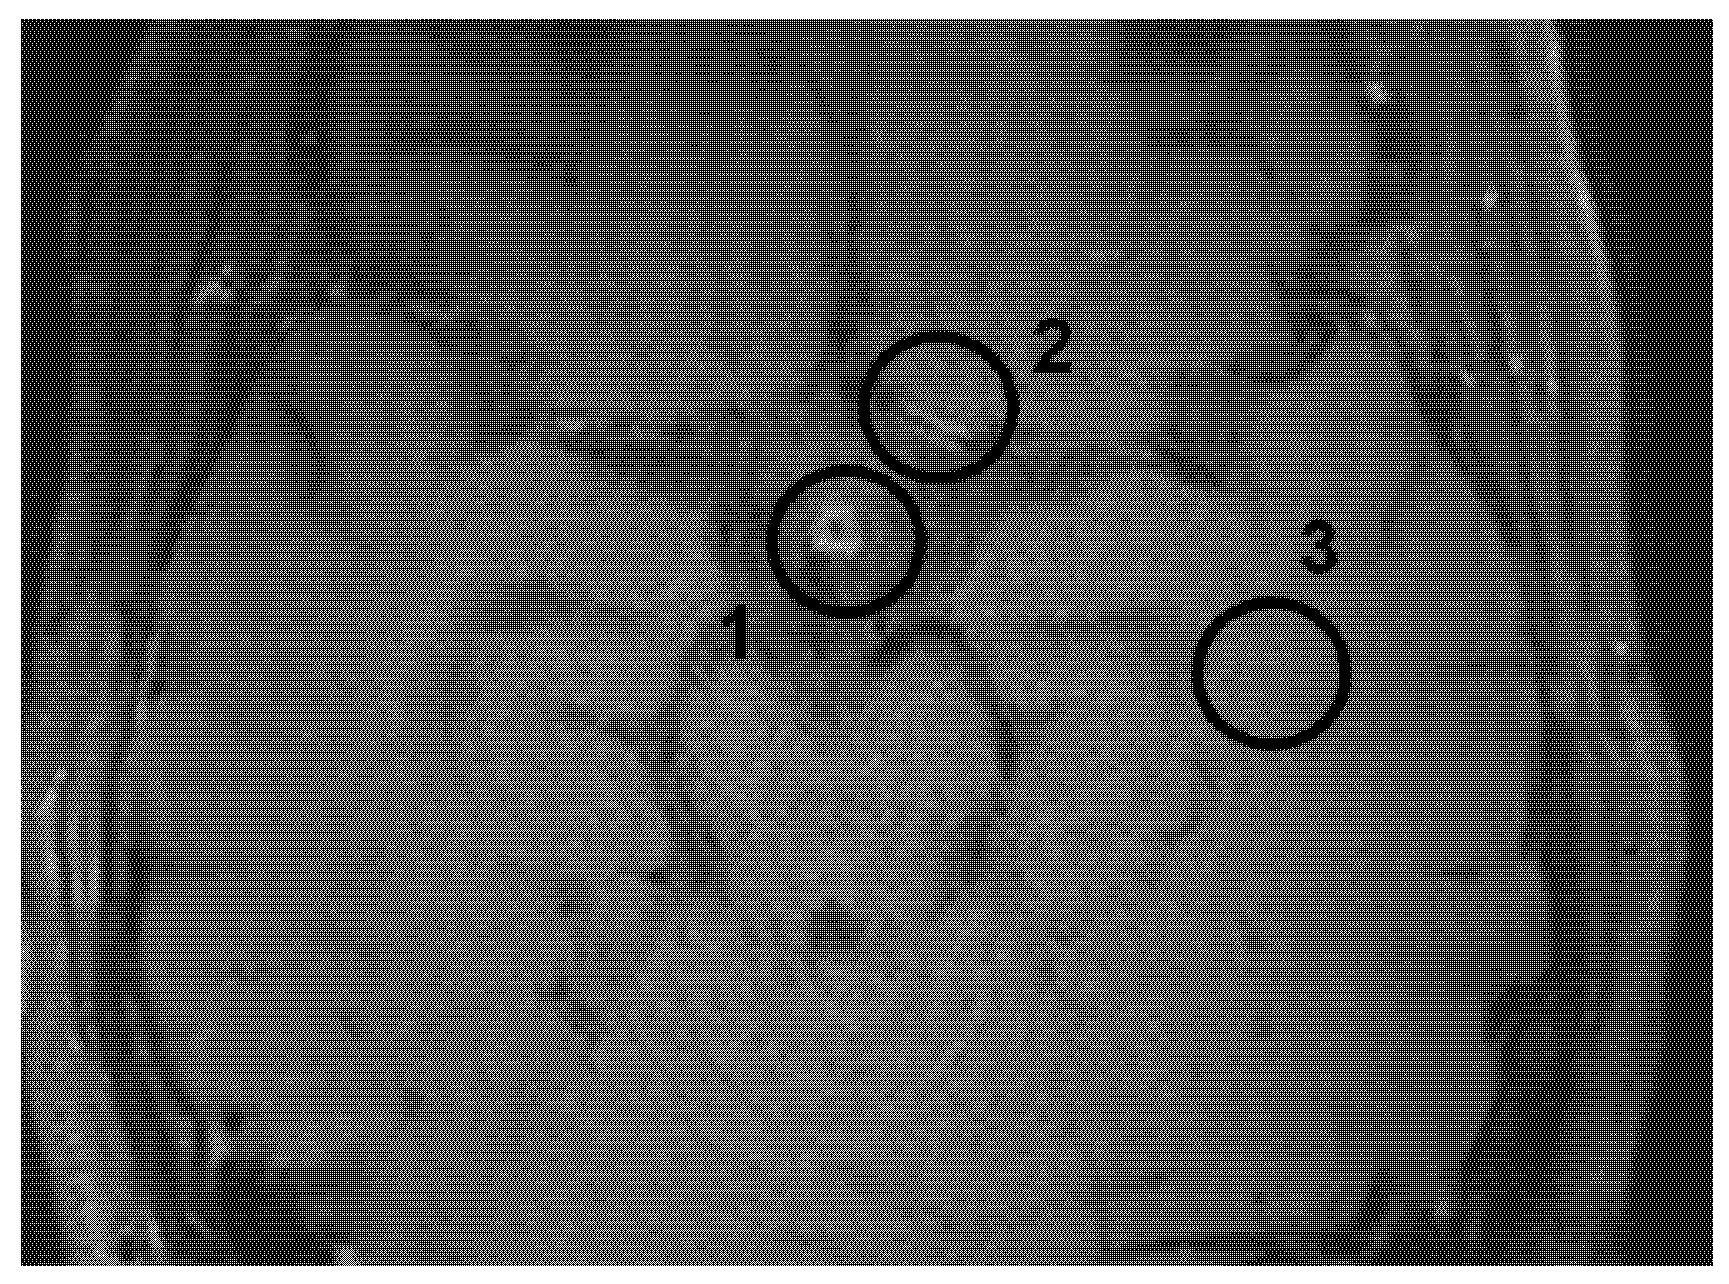

2.3. Measurements

3.2. Signal Intensity of Pituitary Stalk and White Matter of the Temporal Lobe

3.3. Analysis of MRI Performed on the Same MR Machine

3.4. Analysis of MRI Performed on Different MR Machines